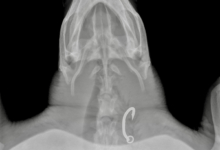

Dhontha is in overall good body condition and her blood work is acceptable, but her X-rays showed something alarming: She has a large hook lodged in her oesophaghus that will require surgical removal.